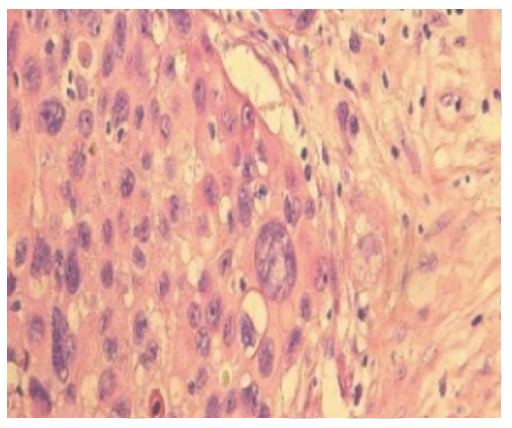

Zhao J, Zheng J, Kong M, et al. Advanced lung adenocarcinomas with ROS1-rearrangement frequently show hepatoid cell[J]. Oncotarget, 2016, 7(45): 74162-74170. DOI: 10.18632/oncotarget.12364.

pmid: 27708233